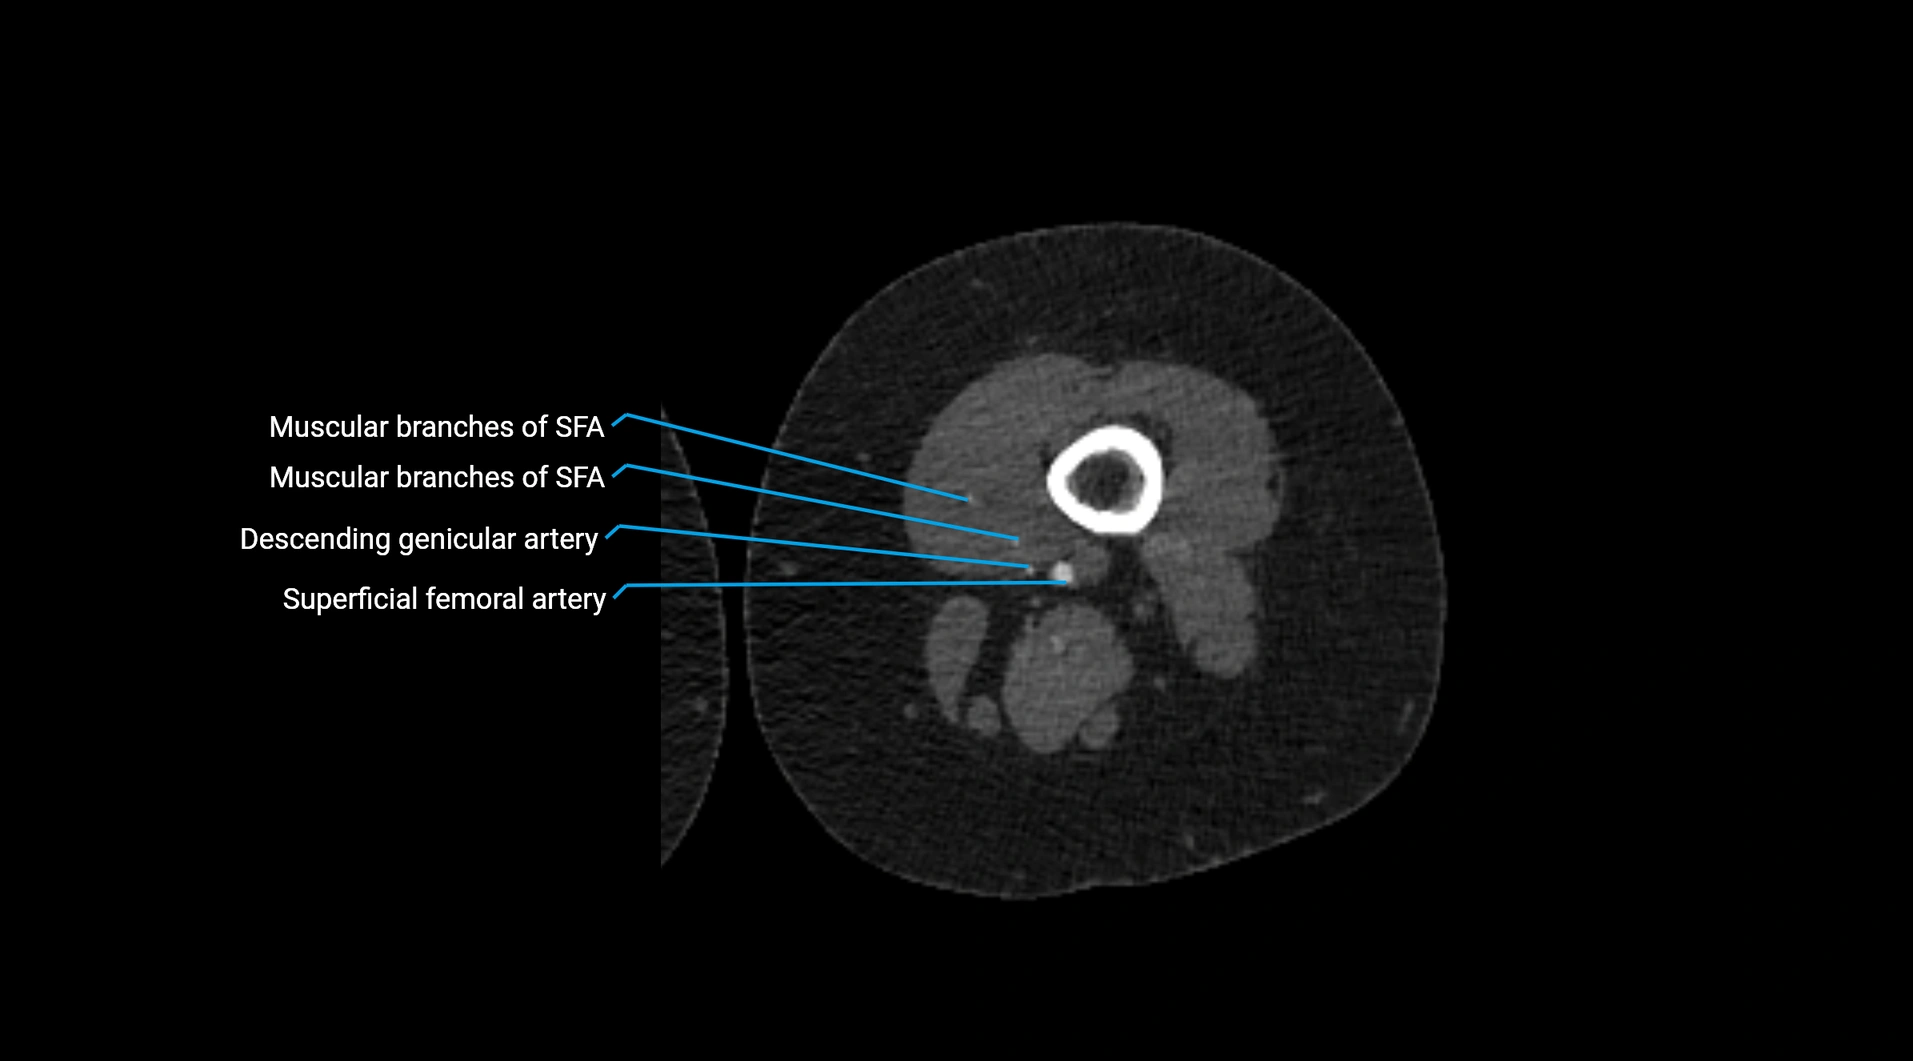

CT images

image